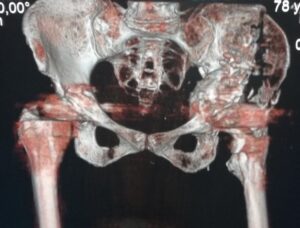

- Σοβαρό περιπροθετικό κάταγμα κοτύλης, όπου δημιουργήθηκε stress riser (αυξημένη συγκέντρωση φορτίων ) στο πέρας του ενισχυτικού δακτυλίου και έγινε καταγματική γραμμή από το εμφύτευμα σε όλη τη διαδρομή του λαγονίου οστού!!!